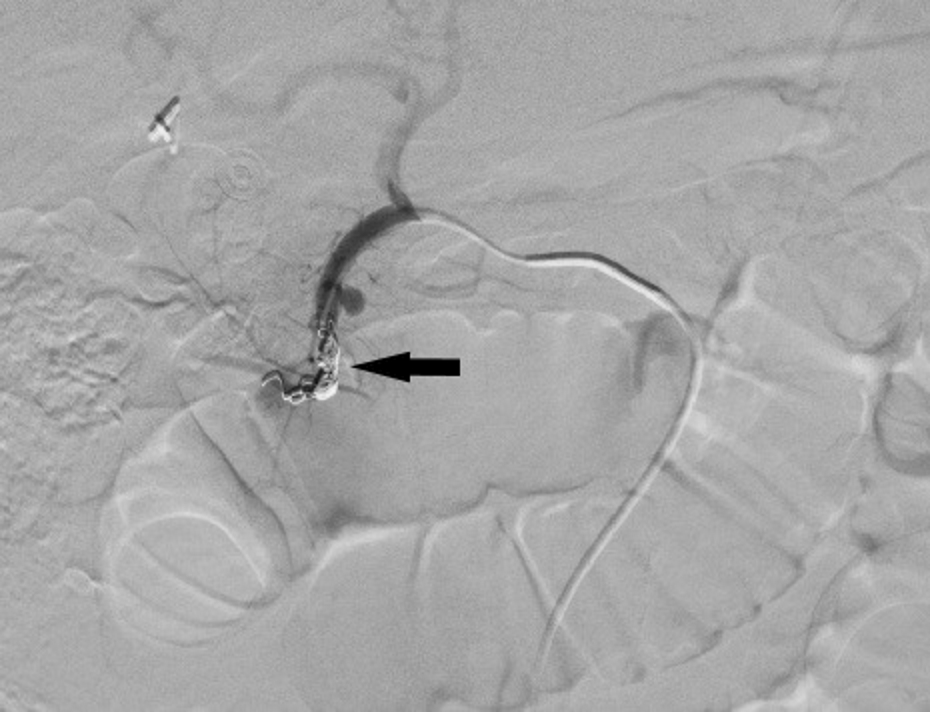

From www.researchgate.net

Initial treatment Coil embolization. (A) A TransForm C 4 mm ? 10 mm Coil Embolization Of Gda The best coil position within the gda is as close to the main hepatic artery as possible to exclude perfusion of small pancreaticoduodenal side. We report successful coil embolization of a ruptured gda pseudoaneurysm in a patient with massive gi. Gastroduodenal artery (gda) pseudoaneurysms are among the rarest forms of vapa (<2%). Additionally, it may be done for gda pseudoaneurysms. Coil Embolization Of Gda.